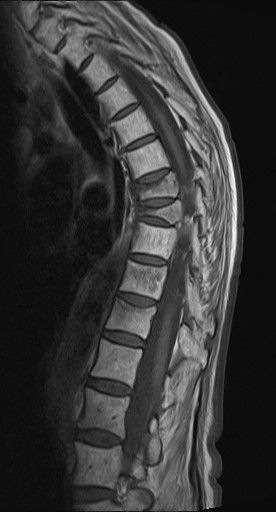

Osteoporose bedeutet wörtlich "poröser Knochen". Es handelt sich um eine systemische Skeletterkrankung, die durch eine niedrige Knochenmasse und eine mikroarchitektonische Verschlechterung des Knochengewebes charakterisiert ist. Die Knochen werden brüchiger und anfälliger für Brüche, die schon bei geringfügigen äußeren Anlässen wie Stürzen oder Stößen oder sogar unter Alltagsbelastungen auftreten können. Die häufigsten Stellen für Osteoporose-bedingte Brüche sind die Wirbelkörper in der Lendenwirbelsäule, der Oberschenkelhals und die Speiche im Handgelenk (Radiusfraktur). Sind bereits Brüche als Folge der Osteoporose aufgetreten, so liegt eine manifeste Osteoporose vor. Die Symptome der Osteoporose sind durch Knochenbrüche und ihre Folgen geprägt, die zu einer deutlichen Einschränkung der Lebensqualität führen, insbesondere bei hüftnahen Frakturen. Es gibt keine eindeutigen Beschwerden der Osteoporose, die Brüchen vorausgehen.

Die Diagnose einer Osteoporose stützt sich auf eine niedrige Knochendichte als messbaren Faktor einer Osteoporose. Die Knochendichtemessergebnisse sind mit dem Frakturrisiko assoziiert. Der Goldstandard zur Knochendichtemessung ist die Dual-Energy X-Ray Absorptiometry (DXA). Dabei wird ein Wert ermittelt, der als T-Wert bezeichnet wird und angibt, wie stark die Knochendichte vom Durchschnittswert eines jungen Erwachsenen abweicht. Ein T-Wert von -2,5 oder niedriger bedeutet messtechnisch eine Osteoporose. Zusätzlich werden weitere Untersuchungen wie Blut- und Urinuntersuchungen durchgeführt, um mögliche andere Ursachen für den Knochenabbau auszuschließen. Die auf der DXA beruhende Definition der Osteoporose gilt erst nach Ausschluss anderer Erkrankungen, die mit einer Verminderung des Knochenmineralgehalts einhergehen können. Das Frakturrisiko wird neben der Knochendichte von weiteren Risikofaktoren beeinflusst.

5. ggf. bildgebende Diagnostik bei Hinweisen auf osteoporotische Wirbelkörperfrakturen